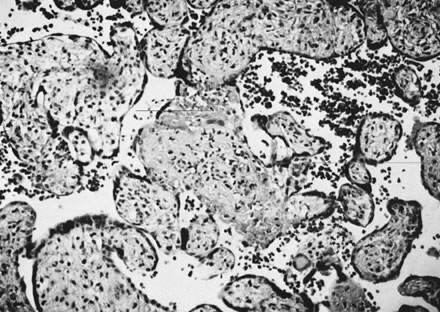

Placental infections via the maternal bloodstream, hematogenous infections, are most often associated with villitis, inflammation of the placental villi. Acute villitis and decidual and villous microabscesses are caused by maternal bacterial sepsis, most commonly with Listeria monocytogenes. Maternal viral infections are more often associated with chronic villitis or chronic choriodeciduitis and/or amnionitis (Fig. 10).37 Chronic chorioamnionitis may also be caused by chronic bacterial infections such as syphilis. In chronic villitis, the inflammatory cell types may differ between infectious agents but unfortunately are not specific for different etiologic agents. Cytomegalovirus also can damage villous endothelium, and affected villi may have variable amounts of hemosiderin, reflecting fetal vascular injury. Granulomatous villitis may be caused by various viruses, mycobacteria, fungus, or parasitic agents. Chronic umbilical vasculitis, including sclerosing funisitis with perivascular calcification, may also be caused by viral and chronic bacterial infections.38,39,40 Case reports continue to expand the range of fetal anomalies seen in early ToRCH and related viral infections, including varicella zoster.

Fig. 10. Placenta of infant with microcephaly and cytomegalic inclusion disease. Typical intranuclear inclusion ( arrow) in a background of chronic inflammation and vascular obliteration (hematoxylin and eosin, ×400).